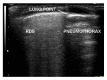

Background. Pneumothorax (PTX) still remains a common cause of morbidity in critically ill and ventilated neonates. At the present time, lung ultrasound (LUS) is not included in the diagnostic work-up of PTX in newborns despite of excellent evidence of reliability in adults. The aim of this study was to compare LUS, chest X-ray (CXR), and chest transillumination (CTR) for PTX diagnosis in a group of neonates in which the presence of air in the pleural space was confirmed. Methods. In a 36-month period, 49 neonates with respiratory distress were enrolled in the study. Twenty-three had PTX requiring aspiration or chest drainage (birth weight 2120 ± 1640 grams; gestational age = 36 ± 5 weeks), and 26 were suffering from respiratory distress without PTX (birth weight 2120 ± 1640 grams; gestational age = 34 ± 5 weeks). Both groups had done LUS, CTR, and CXR. Results. LUS was consistent with PTX in all 23 patients requiring chest aspiration. In this group, CXR did not detect PTX in one patient while CTR did not detect it in 3 patients. Sensitivity and specificity in diagnosing PTX were therefore 1 for LUS, 0.96 and 1 for CXR, and 0.87 and 0.96 for CTR. Conclusions. Our results confirm that also in newborns LUS is at least as accurate as CXR in the diagnosis of PTX while CTR has a lower accuracy.